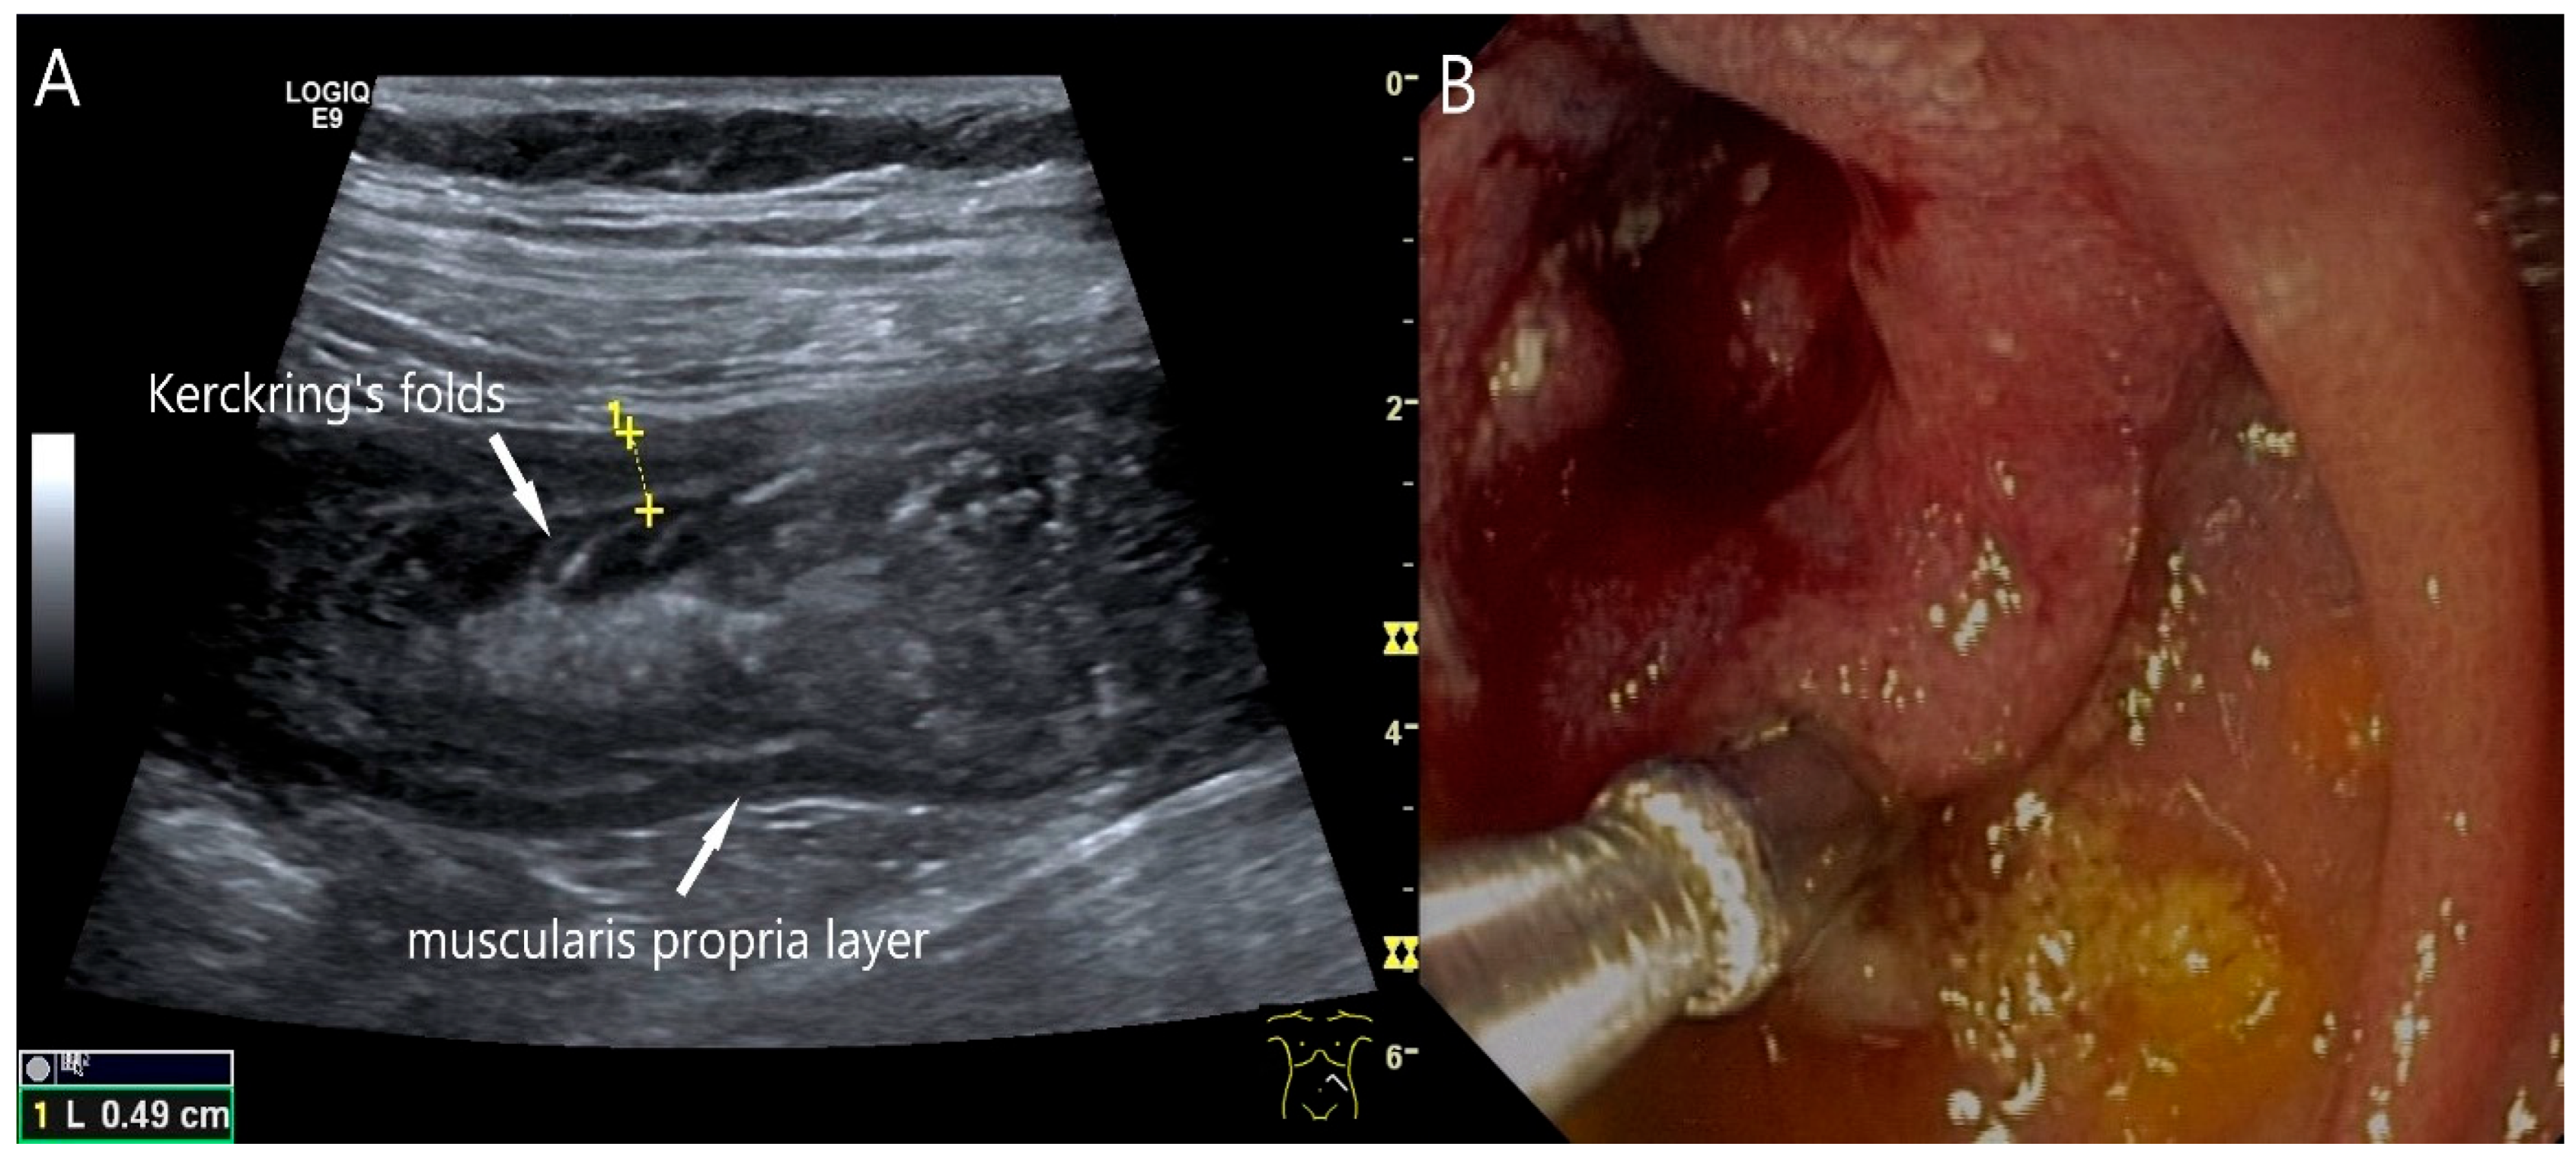

Figure 22.

Jejunal wall hematoma with a Quick ratio <5%. Smoothly defined, distinct wall thickening and lumen obstruction. The wall stratification is indistinct, slightly hyperechoic, and clearly blurred and unfocused (a). The Kerckring folds are thickened and also very blurred (b).